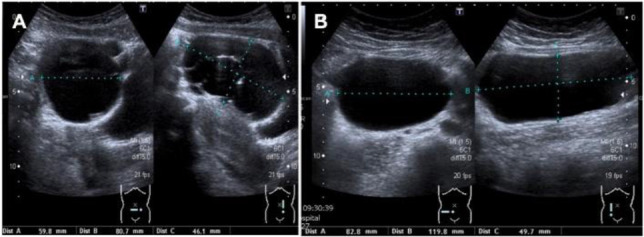

Case presentation: A 16-year-old nulliparous female was admitted with persistent lower abdominal pain and bloating. A pelvic magnetic resonance imaging showed large bilateral cystic and multiloculated adnexal masses arising from her ovaries. Her tumor markers were normal. The patient underwent three seperate ovarian cystectomies over a seven-year period from the age of sixteen due to recurrent large bilateral benign ovarian mucinous cystadenomas. Repeated histological examinations were the same after each case. Given her age and the history of multiple ovarian surgeries, she was referred to the fertility clinic to explore options for oocyte cryopreservation.